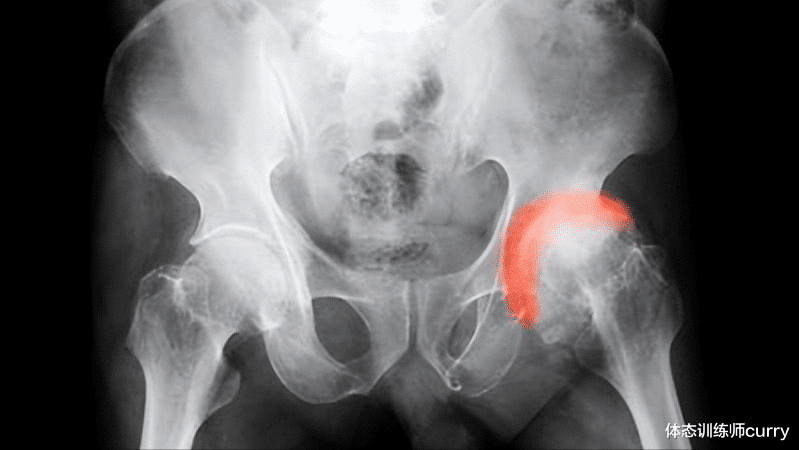

一、股骨头是哪里 , 为什么会发生股骨头坏死?股骨头 , 顾名思义 , 就是股骨的“头部”位置 。 股骨就是我们俗称的大腿骨 。 在大腿骨顶端 , 有一个呈半球状的部分 , 它就是股骨头 。 股骨头和其对侧的髋臼组成髋关节 , 也就是我们常说的“大胯” 。

股骨头坏死 , 一般也称为股骨头缺血性坏死 。 它是骨科最常见的难治性疾病之一 。 股骨头坏死病因较为复杂 , 但可以做如下简单描述:即股骨头因外伤或其他原因 , 供血发生中断 , 骨细胞以及骨髓成分因为缺少血液供养而死亡 。 这会使股骨头的结构发生病理性改变 , 股骨头塌陷 , 从而发生关节功能障碍 。

股骨颈位于股骨头下方 , 连接股骨头与股骨骨干 , 是较为狭窄的部分 。 股骨头的血液供应主要依靠外骺动脉和下骺动脉 , 也与股骨颈内的髓动脉及圆韧带动脉有关 。 股骨颈骨折会导致股骨头、颈移位 , 外骺动脉受损、断裂 , 股骨头供血不足 , 继而出现坏死 。